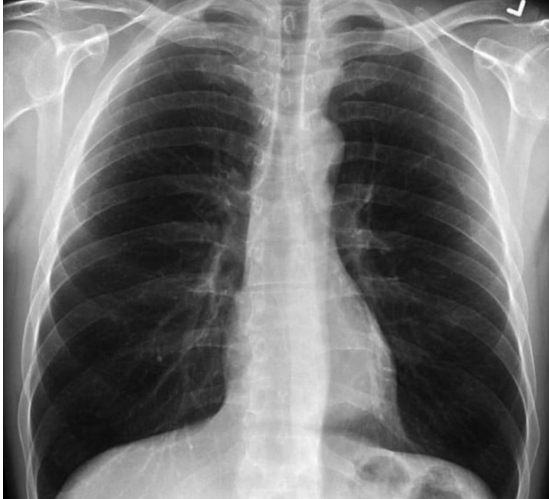

Одно изображение показывает нормальную здоровую пару легких, другое - легкие курильщика, а третье - легкие пациента с коронавирусом.

Легкие здорового человека